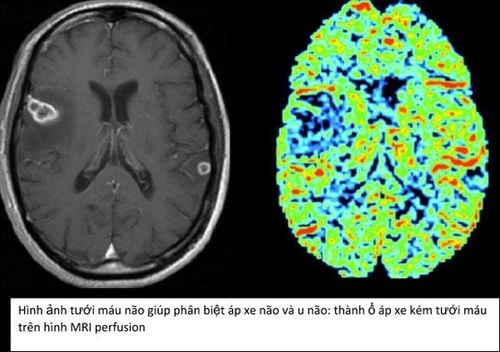

Chụp MRI tưới máu não là kỹ thuật cao, giúp đánh giá chi tiết tình trạng lưu lượng máu tới các vùng não, rất hữu ích trong chẩn đoán và theo dõi bệnh lý mạch máu não, đột quỵ hoặc u não.